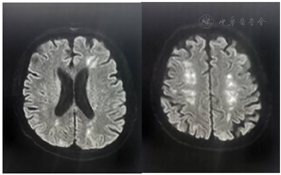

继续予患者有创呼吸机辅助通气,因血流动力学不稳定(低血压、氧饱和度持续<90%),予置入ECMO辅助循环,同时予抗感染、抑酸、抗凝等治疗。针对暴发性心肌炎,予糖皮质激素冲击(甲基强的松龙500 mg/d,共2 d)和丙种球蛋白(20 g/d,共4 d)调节免疫。经上述治疗后患者血流动力学稳定,血压130~140/60~70 mmHg,血乳酸1~2 mmol/L,氧分压90~100 mmHg。监测EOS和hscTnI最初呈下降趋势,但入心内监护室后第3日EOS和hscTnI较前再次升高,故第3日将甲基强的松龙加至1000 mg,其后监测EOS和hscTnI仍继续升高。考虑患者暴发性心肌炎继发于高嗜酸性粒细胞增多综合征(hypereosinophilic syndromes,HES)可能性大,请血液科会诊后,筛查原发性HES、继发性HES和嗜酸性肉芽肿性多血管炎(查ANCA阴性,不支持)。原发性HES方面:行骨髓穿刺和活检,并送检全外显子测序和融合基因,包括FIP1L1-PDGFRA融合,PDGFRB,FGFR1,PCM1-JAK2融合等,均为阴性。继发性HES方面,查血白介素-5(IL-5)未见升高(糖皮质激素治疗2 d后),外送多种寄生虫抗体阴性,血IgE不高,全身浅表淋巴结超声未见异常,入院后曾行胸部CT和腹部超声未见实体肿瘤证据。患者无原发性和继发性HES证据,考虑为特发性HES,但对糖皮质激素反应不佳、治疗相对困难。根据EOS计数,逐渐加用羟基脲、芦可替尼、环磷酰胺和依托泊苷,并将甲基强的松龙逐渐减量,患者EOS和hscTnI均呈逐渐下降趋势。患者心功能亦逐渐恢复,ECMO辅助1周后复查超声心动图,左心室射血分数恢复至60%,予撤除ECMO。撤除ECMO后复查超声提示下腔静脉条状血栓(图1),继续抗凝治疗。但患者撤除ECMO、停用镇静药物后意识状态界于醒状昏迷至微小意识状态之间,可自主睁眼,呼之不应,四肢无肌力和肌张力,复查头颅MRI提示双侧多发脑梗死,较前明显增多,梗死部位以分水岭为主(图2)。患者意识持续不恢复,予气管切开、人工鼻通气,转回神内科进一步治疗。

患者转回神内科后治疗包括:1.HES原发病治疗。糖皮质激素规律减量,继续羟基脲、芦可替尼,甲基强的松龙减至12 mg每日1次时EOS计数再次升高,间断予环磷酰胺和依托泊苷。2.对症支持治疗。包括抗感染、营养支持、肢体锻炼等。患者意识持续不恢复,反复肺部感染,痰培养提示多种耐药菌,于2021年12月死于肺部感染。